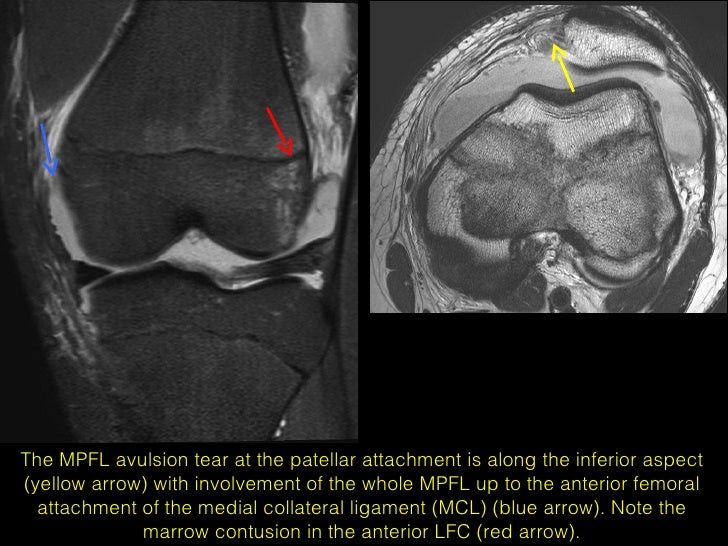

(Fig 4A.30) Complete MPFL Tear at Femoral Origin

(Fig 4A.30) Complete MPFL Tear at Femoral Origin - This is generally considered a minor injury that can be treated conservatively. The knee may have to be immobilized in a splint for a. The medial patellofemoral ligament (mpfl) is a ligament that prevents your patella (kneecap) from dislocating to the outside of your knee. To thoroughly check the structures in the knee and assess other injuries, every surgery includes. You should also read this: Can Drinking Too Much Water Affect Pregnancy Test